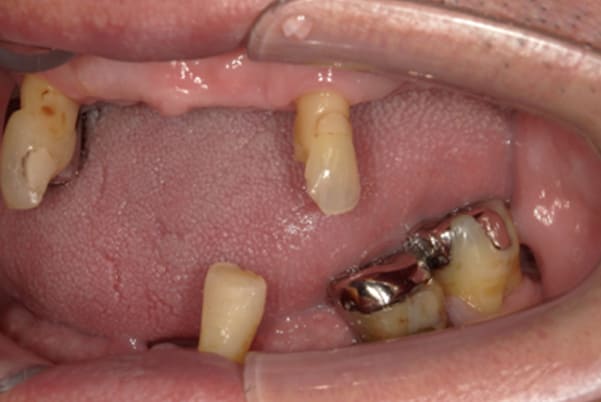

症例レポート[CASE.02]

入れ歯がカパカパして痛い、

歯がぐらぐらする

- 男性(60代)

- 入れ歯がカパカパする、歯がぐらぐらして痛い、食いしばれない

- 上顎精密総金属床総入れ歯

- 下顎精密金属床部分入れ歯

- ジルコニアクラウン4歯

- 上顎精密総金属床総入れ歯:55万円

- 下顎精密金属床部分入れ歯:55万円

(ミリング、ラベット加工込み) - ジルコニアクラウン:11万円×4歯

合計:154万円(税込)

上の前歯が重度歯周病により動揺し、残せない状態のため、入れ歯も動揺がありました。

ご自身の歯に負担の少ないバネ、また見た目も改善

バネをかける歯は繋げることで強度を増し、歯への負担を軽減し、歯の寿命を長くする設計へ。

バネがかかる歯の被せ物は、歯への負担を減らし、入れ歯が動きにくいようになる形態をあらかじめ付与することで、より入れ歯の機能が高まります。

治療を行う際、被せ物や入れ歯は、別々に考えるのではなく、一口腔単位としてお口全体のことを考え最良の治療計画を立てることが歯の寿命、機能効果を向上させるため、専門医としてこのことは常に心掛けて治療を行っています。

残りの歯に負担がかからないよう、被せ物と入れ歯の一体化を図った入れ歯

治療前は上下奥歯の入れ歯が削れていることで、かみ合わせが低くなり唇もつむった状態でした。

かみ合わせを適切な高さに戻したことで、本来の自然な口元へ。